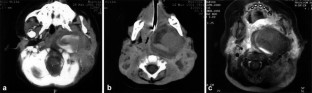

Giant mycotic aneurysm of the internal carotid artery in a child: endovascular treatment

We present a case of a giant mycotic aneurysm of the left internal carotid artery in a child, the result of direct extension of a deep neck space infection. This lesion is life threatening and may put the patient at risk of unwarranted biopsy or drainage if not recognized. Diagnosis and treatment planning rely heavily on cross-sectional imaging, and angiography is frequently necessary. This case is unique for two reasons: (1) we present for the first time the MRI findings and (2) we describe an alternative to surgical ligation -- neurointerventional embolotherapy. Minimally invasive transcatheter embolization was successfully performed on our patient to occlude the abnormal left internal carotid artery segment.

Fig. 3.

Fig. 4.